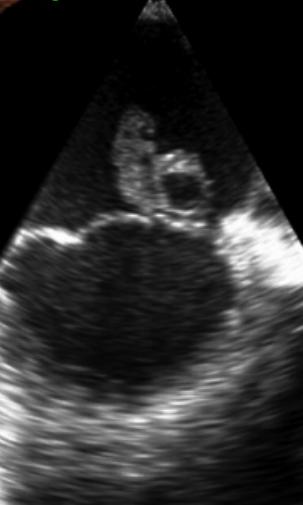

Case Presentation: A 30 year-old female presented postpartum day 1 following a normal vaginal delivery from an outside hospital after chest CT angiography (CTA) identified a 2.5 cm pericardial effusion. Review of systems was positive for dry cough, left sided chest pain, dyspnea on exertion, recent post-partum abdominal pain, chills, and diaphoresis. On arrival to the medicine floor, she was afebrile, BP: 140/83 without pulsus paradoxus, HR 100 bpm, RR 20, and normal O2 saturation on room air. Physical exam revealed rales at the lung bases, bilateral pedal edema, and JVD to angle of the mandible. Labs were significant for a WBC 22,700, procalcitonin of 1.78, ESR 52, CRP 128, BNP of 587, and troponin peak of 0.110. EKG showed no ST changes and was without electrical alternans. On initial evaluation, a bedside Point of Care Ultrasound (POCUS) exam of the heart was performed, which was concerning for ~2 cm vegetation on the mitral valve (POCUS Mitral Vegetation Image). As a result, the patient was immediately started on empiric vancomycin and piperacillin-tazobactam due to concern for sepsis from infective endocarditis (IE). A formal TTE performed the following morning confirmed a vegetative mass measuring 2.2 cm x 1.5 cm on the anterior leaflet of the mitral valve with mitral regurgitation, dilated left atrium, and pericardial effusion. TEE further confirmed the presence of a large vegetative mass with multiple echolucencies suggestive of valvular abscess (TEE Mitral Vegetation Image) . Blood cultures came back positive for Streptococcus mitis/oralis . Cardiothoracic Surgery was consulted and performed an immediate mitral valve repair with abscess extraction. She was discharged home with 6 weeks of IV ceftriaxone and follow up with Infectious Disease. It is important to note, the baby was also tested and luckily the blood cultures remained negative at > 5 days.